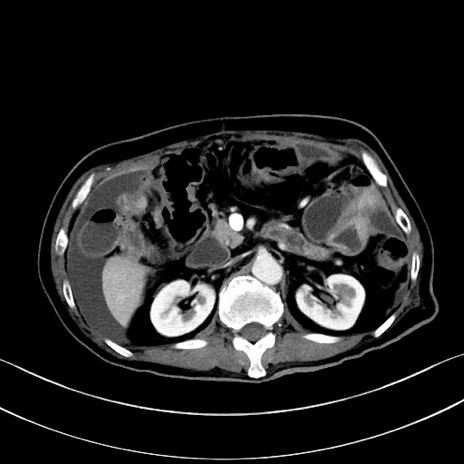

症例28(横断像)

【症例】60歳代男性

【主訴】嘔吐

【現病歴】胃癌にて胃全摘後。食思不振が悪化し、夜中に嘔吐することがある。

【既往歴】胃癌、胃全摘、脾摘、胆摘後

【データ】WBC 5900、CRP 10.56